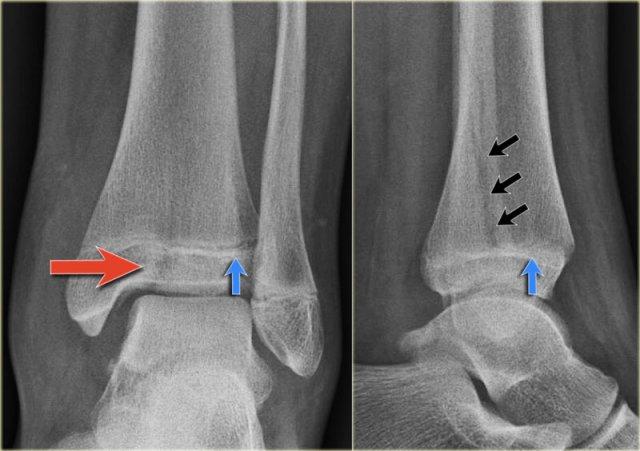

Các hình ảnh cho thấy một trường hợp gãy Weber B rõ ràng.

Trên tư thế thẳng (AP), đường thấu quang dạng tuyến tính là dấu hiệu gợi ý gãy tertius (mũi tên đỏ).

Dấu hiệu này xuất hiện do sự lệch trục nhẹ của mảnh gãy.

Tương tự, trong một số trường hợp, sự lệch trục có thể tạo ra một đường tăng tỷ trọng dạng tuyến tính.

Trong trường hợp này, có gãy Weber B kèm theo bong điểm bám mắt cá trong.

Đường tăng tỷ trọng trên tư thế thẳng (AP) gợi ý một mảnh gãy tertius lớn.

Gãy tertius này cũng có thể thấy trên tư thế nghiêng, nhưng trong nhiều trường hợp chúng ta cần kết hợp thông tin từ cả hai tư thế nghiêng và thẳng để chẩn đoán gãy tertius.

Đây là thêm một số ví dụ về đường tăng tỷ trọng gợi ý gãy tertius.

Phù nề phần mềm cả hai bên trong và ngoài (mũi tên đỏ).

Đặc biệt, phù nề phía trong nên gợi ý khả năng chấn thương xoay ngoài – sấp (Weber C). - Đường thấu quang trên tư thế Mortise (mũi tên đen) và tư thế nghiêng. Dấu hiệu này nên gợi ý gãy tertius.